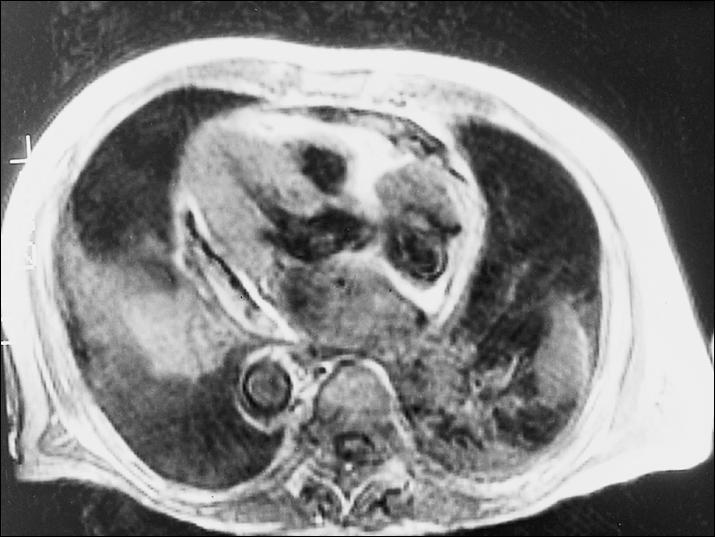

RA的缩窄性心包炎MRI图。心包与灰色心肌之间白色致密浸润为心包液。